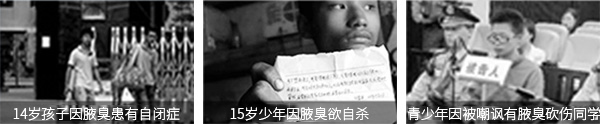

孩子年龄尚小,身心尚显稚嫩,因此很多家长并不重视。儿童皮肤敏感,很多家长盲目用药,导致皮肤营养流失严重,间接造成的汗斑、腋毛癣等问题。而更重要的是腋臭对孩子身心造成的危害,更佳超乎我们的想象。

腋臭是不可自愈的,会持续影响儿童的正常交际与生活。临床数据统计,因腋臭患有心理障碍的儿童日益增多,因此医生建议儿童腋臭需要提早治疗,避免悲剧的发生。

不要让这些危害在孩子身上发生

不要让这些危害在孩子身上发生